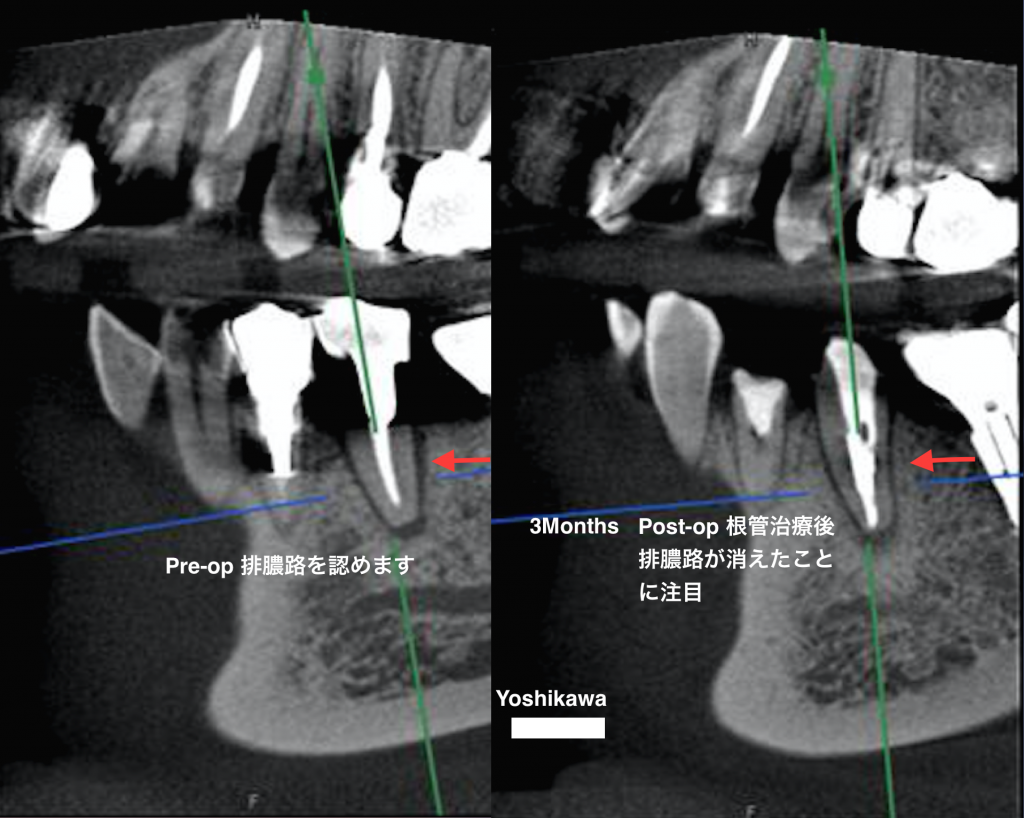

根管治療により排膿路が消えた

歯と骨の間にある歯根膜を通じて外に膿が出ようとして排膿路を形成していましたが、CTとマイクロスコープを使用

した根管治療により治癒傾向を認めました。

下のレントゲンは術後2ヶ月後のものです。